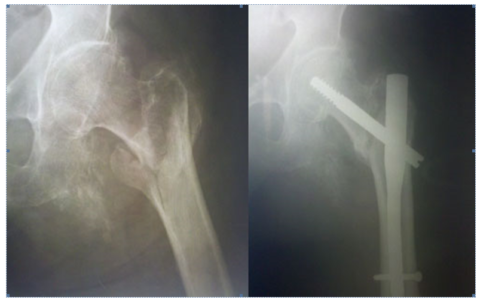

Классификация переломов диафиза бедренной кости: Иллюстрации и информация